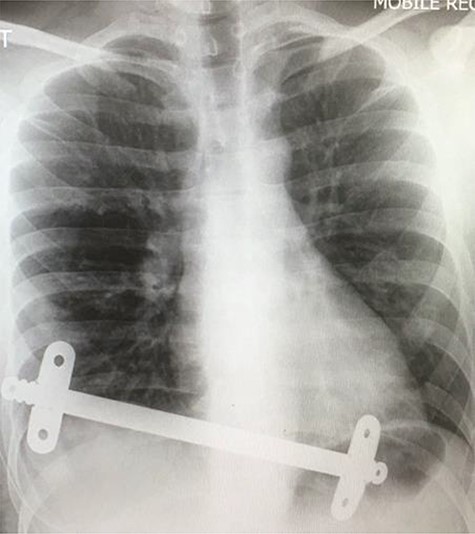

Postoperative chest X-ray following initial Nuss procedure, showing both substernal bars inserted to elevate the depression caused by pectus excavatum.

The patient underwent video-assisted thoracoscopic surgery (VATS) and the modified Nuss- procedure for the surgical correction of his PE. The primary incision was 0.5 cm long along the anterior axillary line of the right lateral chest in the second intercostal space. A 5-mm zero-degree thoracoscope was used to provide clear visualization. An additional 2-cm incision was made, 10 cm underneath the previous incision, where the bar introducer and an 11-inch bar were inserted for correction of the PE. This bar was secured using one stabilizer on each side. An additional second 9-inch Nuss bar was inserted inferior to previous bar with one stabilizer on each side. The procedure was uneventful, and a chest X-ray was performed to confirm adequate substernal bar placement (Fig. 1).